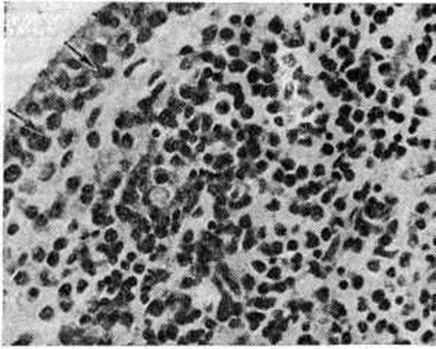

В гистологический картине синовита выделяют следующие изменения: 1) поражение сосудов микроциркуляторного русла; 2) гиперплазию и гипертрофию синовиальных клеток; 3) воспалительную клеточную инфильтрацию; 4) разрастание грануляционной ткани, склероз, липоматоз синовиальной собственной пластинки. Повышается проницаемость стенок сосудов микроциркуляторного русла, сопровождающаяся выходом фибринозного экссудата и образованием очагов фибриноида в синовиальной собственной пластинке и фибриноподобных наложений на поверхности синовиальной оболочки. Иммуноморфологически в очагах фибриноида и в фибриноподобных наложениях выявляются фибрин, иммуноглобулины (G, А, М) и С3-фракция комплемента. При обострении воспаления постоянно отмечается продуктивный или продуктивно-деструктивный васкулит с фиксацией в сосудистой стенке иммуноглобулинов и комплемента. В глубоких слоях синовиальной оболочки (смотри полный свод знаний) изредка определяются ревматоидные узелки — небольшие участки фибриноидного некроза, окружённые макрофагами и лимфоцитами. В 80% случаев встречается гиперплазия и гипертрофия синовиоцитов с характерным палисадообразным их расположением (рисунок 2). С помощью электронно-микроскопического исследования обнаружено, что гипертрофия синовиоцитов происходит за счёт гиперплазии их органелл, особенно зернистой эндоплазматической сети, полисом, аппарата Гольджи и лизосом (рисунок 3). В гиперплазии ворсинчатого слоя синовиальной оболочки участвуют синовиоциты всех трёх типов (А, В и С). На ранних стадиях обострения воспаления клеточная инфильтрация в синовиальной оболочке скудная, представлена лимфоцитами, макрофагами и полиморфно-ядерными лейкоцитами. В дальнейшем отмечается лимфоидно-плазмоцитарная инфильтрация (рисунок 4), иногда с формированием лимфоидных фолликулов. Параллельно при иммунофлюоресцентном изучении Т и В-лимфоцитов синовиальной оболочки при Ревматоидный артрит Банкхерст (A. D. Bankhurst) с соавторами (1976) выявил преобладание Т-лимфоцитов. В синовиальной оболочке отмечается значительная пролиферация фибробластов. В синовиальной собственной пластинке и фиброзном слое наблюдается разрастание грануляционной ткани с исходом в склероз (смотри полный свод знаний) и липоматоз (смотри полный свод знаний).